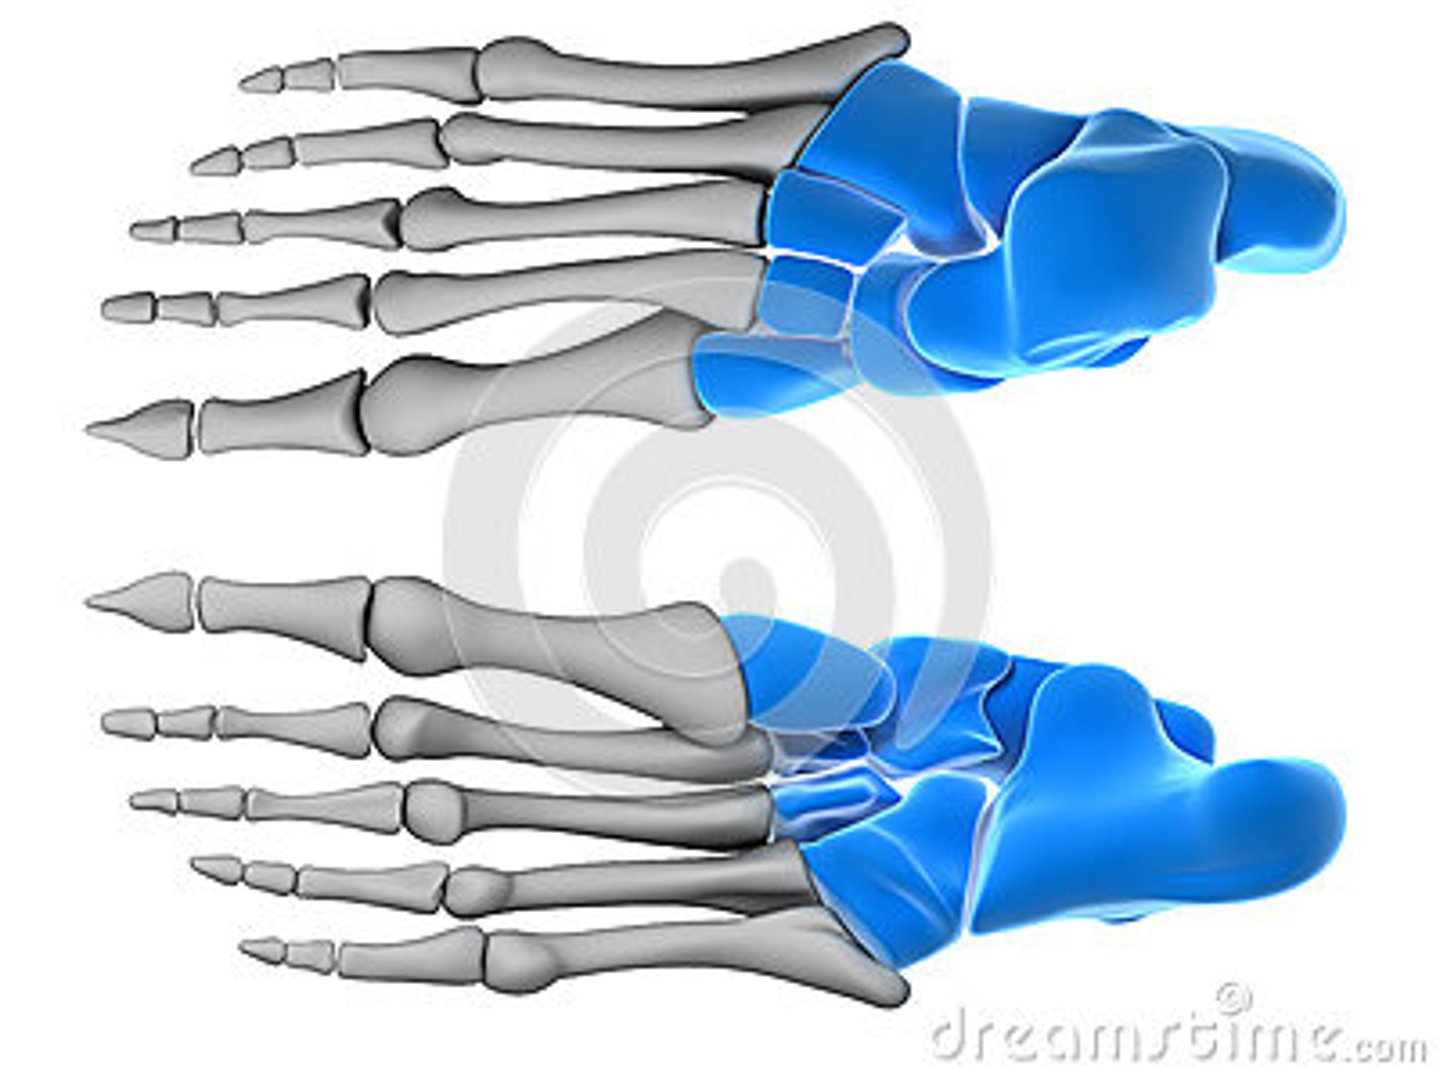

Tarsal Bones

What is the term of the bones highlighted in blue?

Calcaneus

What is the term of the bones highlighted in green?

Talus

What is the term of the bones highlighted in pink?